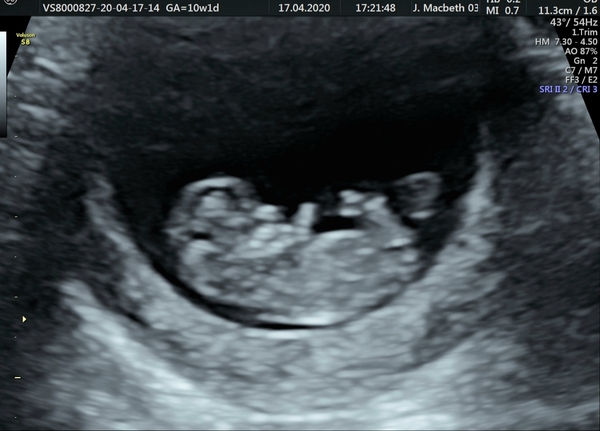

@littlegem638 lovely to see your scan. Congratulations again, so pleased for you.

Just to let you know honey your name and date of birth is at the top of your scan incase you dont want it on here

@trying93 oops! I'm not sure how to remove the photo so i have reported my own photo haha, so i can then upload a cropped version.

Sorry guys had to reload as I didnt crop the image haha.

Exactly 10 weeks today :)

Thank you everyone, being feeling very anxious, I have being a mess today but feel very relieved now x

10 weeks!! Your a quarter of the way there. I hope you can relax a bit now. You give me so much hope

@Trying93 I know! Part of me feels like its flown by but on the other hand I feel like I've being pregnant forever with me losing my other pregnancy in december. I'm going to try my best to be calmer now since seeing baby at this stage has given me confidence x

@Lottieloux thank you! Congrats to you too! This was a private scan as wanted my partner there due to anxiety. I had my booking appointment at 8 weeks then my nhs scan appointment came a week later in the post for when I am exactly 12 weeks, I know that they are saying scans can be anything up to 14 weeks x